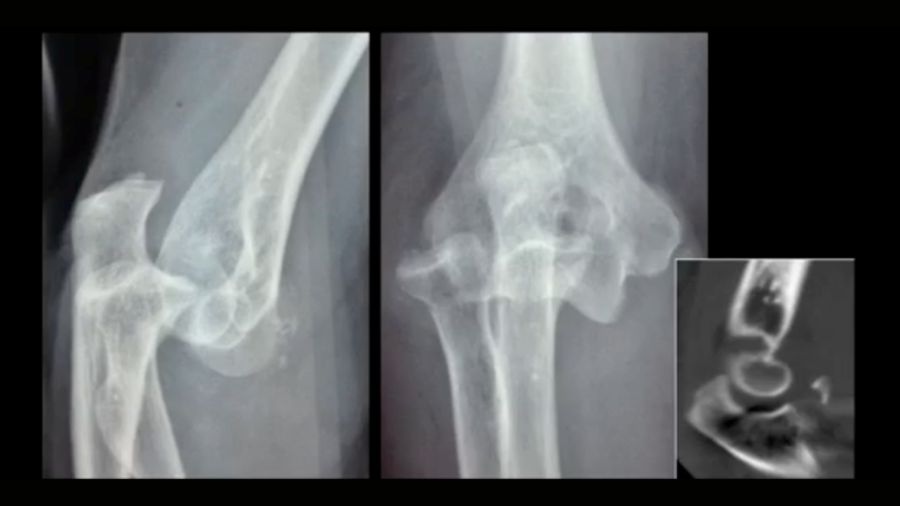

The coronoid fracture: classifying the damage

Shaun O’Driscoll’s coronoid classification system assesses the severity of coronoid fractures. The location and size of the fracture play a critical role in determining the treatment plan. For instance, a radial-sided tip fracture may not have as much impact on stability as a fracture involving the anteromedial facet.

The images demonstrate various coronoid fracture patterns, from minor tip fractures to complex fractures that involve multiple areas of the coronoid. Understanding the exact nature of these fractures—often via CT scans—is essential for effective treatment planning.